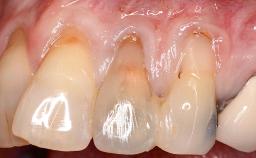

This case demonstrates that a connective-tissue graft in combination with a coronally positioned graft is an effective method of treating cases with peri-implant mucositis and an abutment-level sinus abscess. A 42-year-old man presented with a swelling adjacent to an implant crown at site 21. The swelling had been present for approximately three weeks and was constrained to the buccal and palatal gingival aspects of the implant. A discharge was noted on finger pressure, with localized gingival recession present on the mid- and distolabial aspects of the crown.